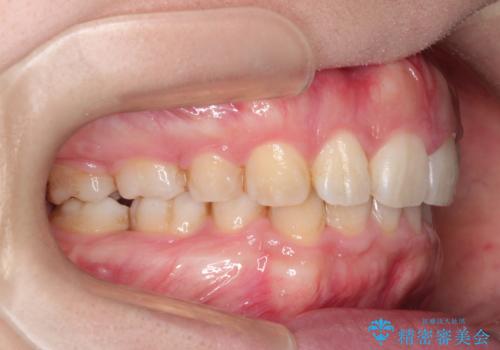

上下の歯のガタガタ ワイヤーでの抜歯矯正で整った歯並びへ

ワイヤーによる抜歯矯正 全体的なガタガタを整った歯並びへ